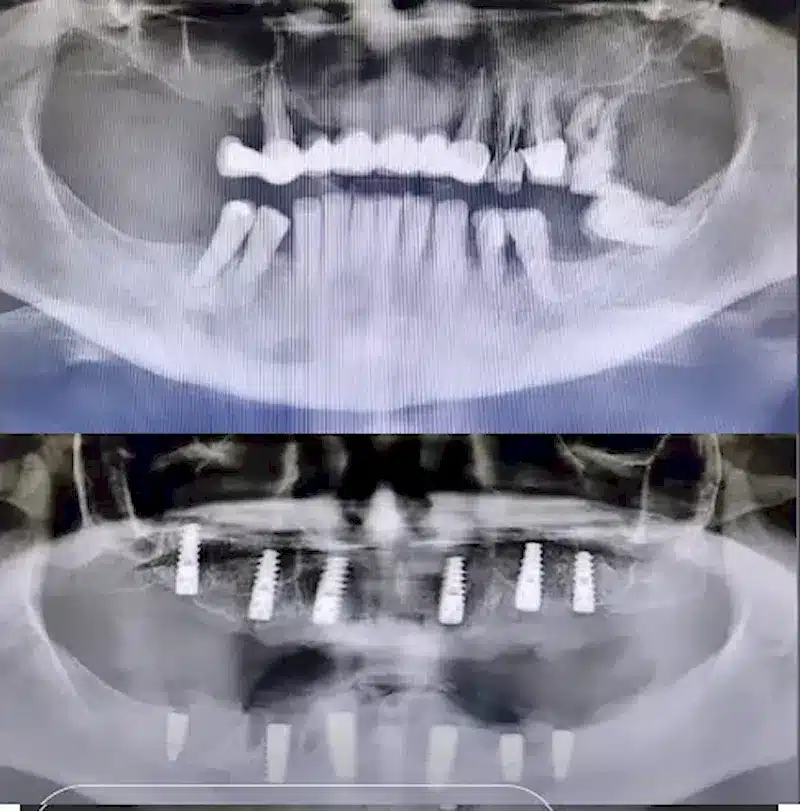

Dr. Seden Aksu is a specialist in modern implantology and surgical dentistry with extensive experience in the management of complex clinical cases. In her practice, she applies comprehensive surgical planning, minimally invasive techniques, and advanced regenerative technologies aimed at restoring both the function of the dentoalveolar system and the aesthetics of the smile. Dr. Aksu has significant experience in performing implant procedures, bone augmentation, and periodontal surgery, including the treatment of patients with severe bone loss. The primary goal of her work is to achieve stable, long-term outcomes in implant rehabilitation and the restoration of oral tissue health.